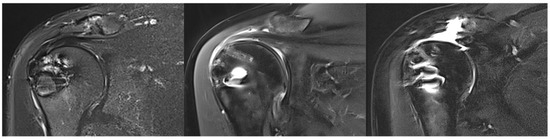

Arthroscopic Bioinductive Collagen Scaffold Augmentation in High-Risk Posterosuperior Rotator Cuff Tears: Clinical and Radiological Outcomes

by Michael Kimmeyer, Geert Alexander Buijze, Madu Nayan Soares, Peter Rab, Antonio Gioele Colombini, Robin Diot, Arno Macken and Thibault Lafosse

Background/Objectives: Bioinductive bovine collagen implants (BCI) have been introduced to enhance tendon biology and promote tissue regeneration in rotator cuff (RC) repairs. This study aimed to assess the clinical and radiological outcomes of arthroscopic posterosuperior rotator cuff (psRC) repair with BCI augmentation in [...] Read more.

Background/Objectives: Bioinductive bovine collagen implants (BCI) have been introduced to enhance tendon biology and promote tissue regeneration in rotator cuff (RC) repairs. This study aimed to assess the clinical and radiological outcomes of arthroscopic posterosuperior rotator cuff (psRC) repair with BCI augmentation in full-thickness tears at increased risk of retear. Methods: This case series analyzed 30 patients with psRC tears who were classified as being at high risk of failure according to a predefined set of parameters, including patient history, radiological findings and intraoperative assessments, and the presence of psRC retears. All patients subsequently underwent arthroscopic psRC repair with BCI augmentation, compromising 21 primary and 9 secondary repairs. Clinical outcomes were assessed using Subjective Shoulder Value (SSV), American Shoulder and Elbow Surgeons (ASES) shoulder score, and Constant score at 6 and 12 months postoperatively. Tendon integrity was assessed using the Sugaya classification. Results: At 12 months, magnetic resonance imaging revealed complete tendon healing in 56.7%, partial healing in 16.7%, and insufficient healing in 26.7%. Significant improvements in SSV (45.3 to 83.5), ASES (40.6 to 77.8), and Constant score (36.6 to 71.7) were observed at 12 months postoperatively, with all outcome measures exceeding their respective minimally clinically important differences. Two patients (6.7%) developed secondary shoulder stiffness, and 1 patient (3.3%) required revision surgery for bicipital groove pain. Conclusions: Augmentation with a BCI in arthroscopic repair of high-risk psRC tears demonstrate promising short-term results. Patients achieve significant improvements in pain and shoulder function, accompanied by satisfactory tendon healing on MRI. Full article

Show Figures

Figure 1